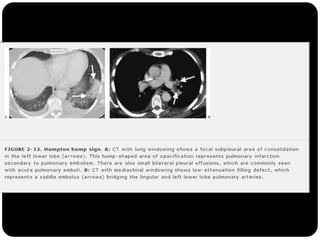

Sinal da corcova de Hampton

O que foivisto até agora?  Cistos (LAM, Histiocistose de Langerhans, PIL)  Bolhas  Cavidades (diss. hemat. de infecção, neoplasia,TB, gran. Wegerner)  Enfisema (centrolobular)  Padrões e sinais torácicos Sinal deWestermark Sinal da corcova de Hampton Sinal de árvore em brotamento Perfusão em mosaico ( X vidro fosco) Faveolamento - fibrose